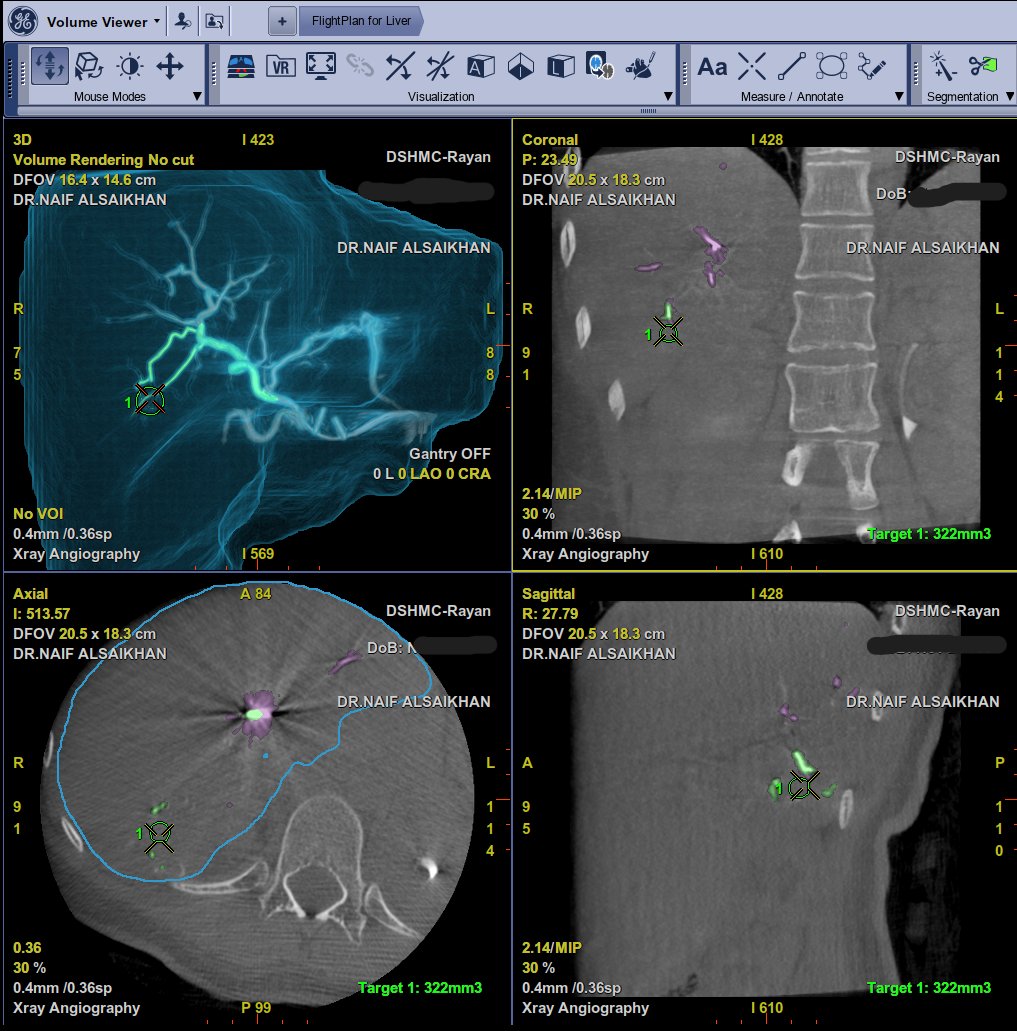

ما هو قسم الاشعة التداخلية ؟ ما هو قسم الانجيو ؟ ما الفائدة منه ؟

سأبدا في هذا الثريد اعرف عن الانجيو ببعض المعلومات وان شاء الله نفيد ونستفيد.